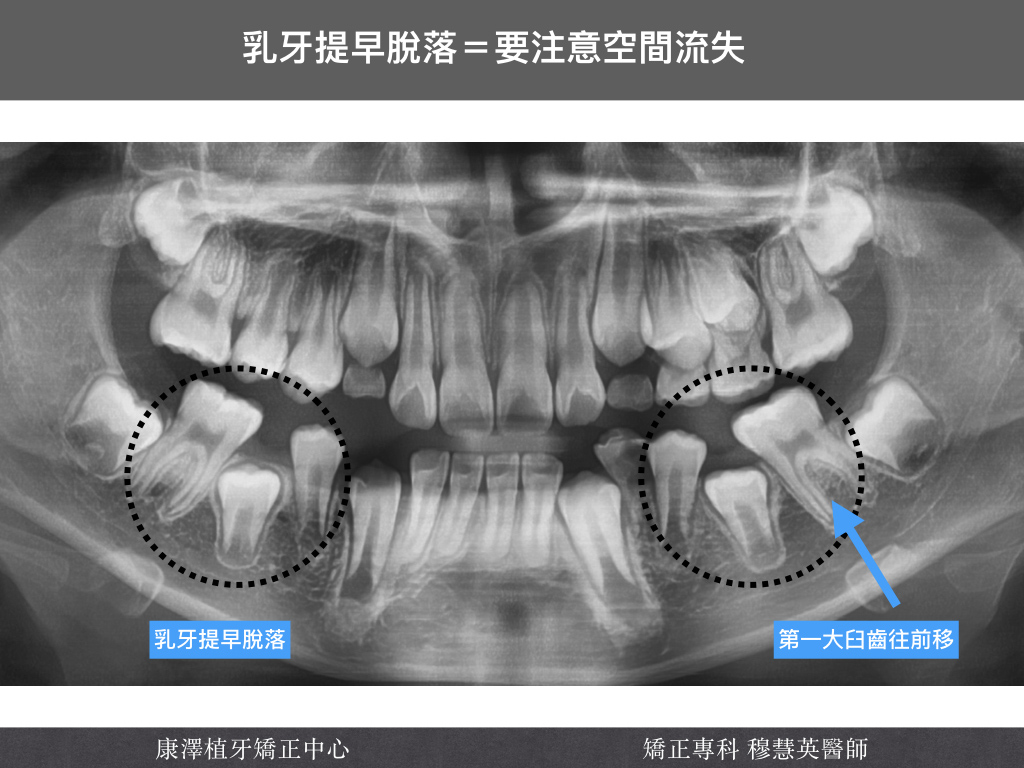

這是一位國小高年級孩子的全口 X 光片:

- 下顎第二乳臼齒提早脫落

- 後方的第一大臼齒向前傾斜,佔據原本的空間

- 導致第二小臼齒萌發受阻,可能無法順利長出來